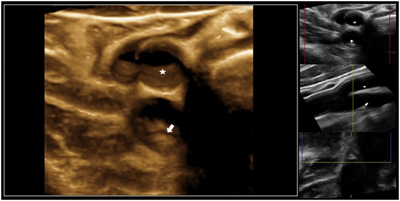

3D de la arteria carótida derecha donde se aprecia una pequeña protrusión en la pared del vaso que corresponde a una placa de aterosclerosis (flecha) en la rama inferior (interna) de la arteria carótida próxima a la zona del bulbo-bifurcación mientras que la rama superior (externa) está libre de enfermedad mostrando una superficie lisa (asterisco).